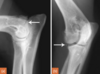

If this is an 8 week old Rottweiler, what are the * indicating?

Future ossification centres of the olecranon (ulna) and medial epicondyle (humerus).